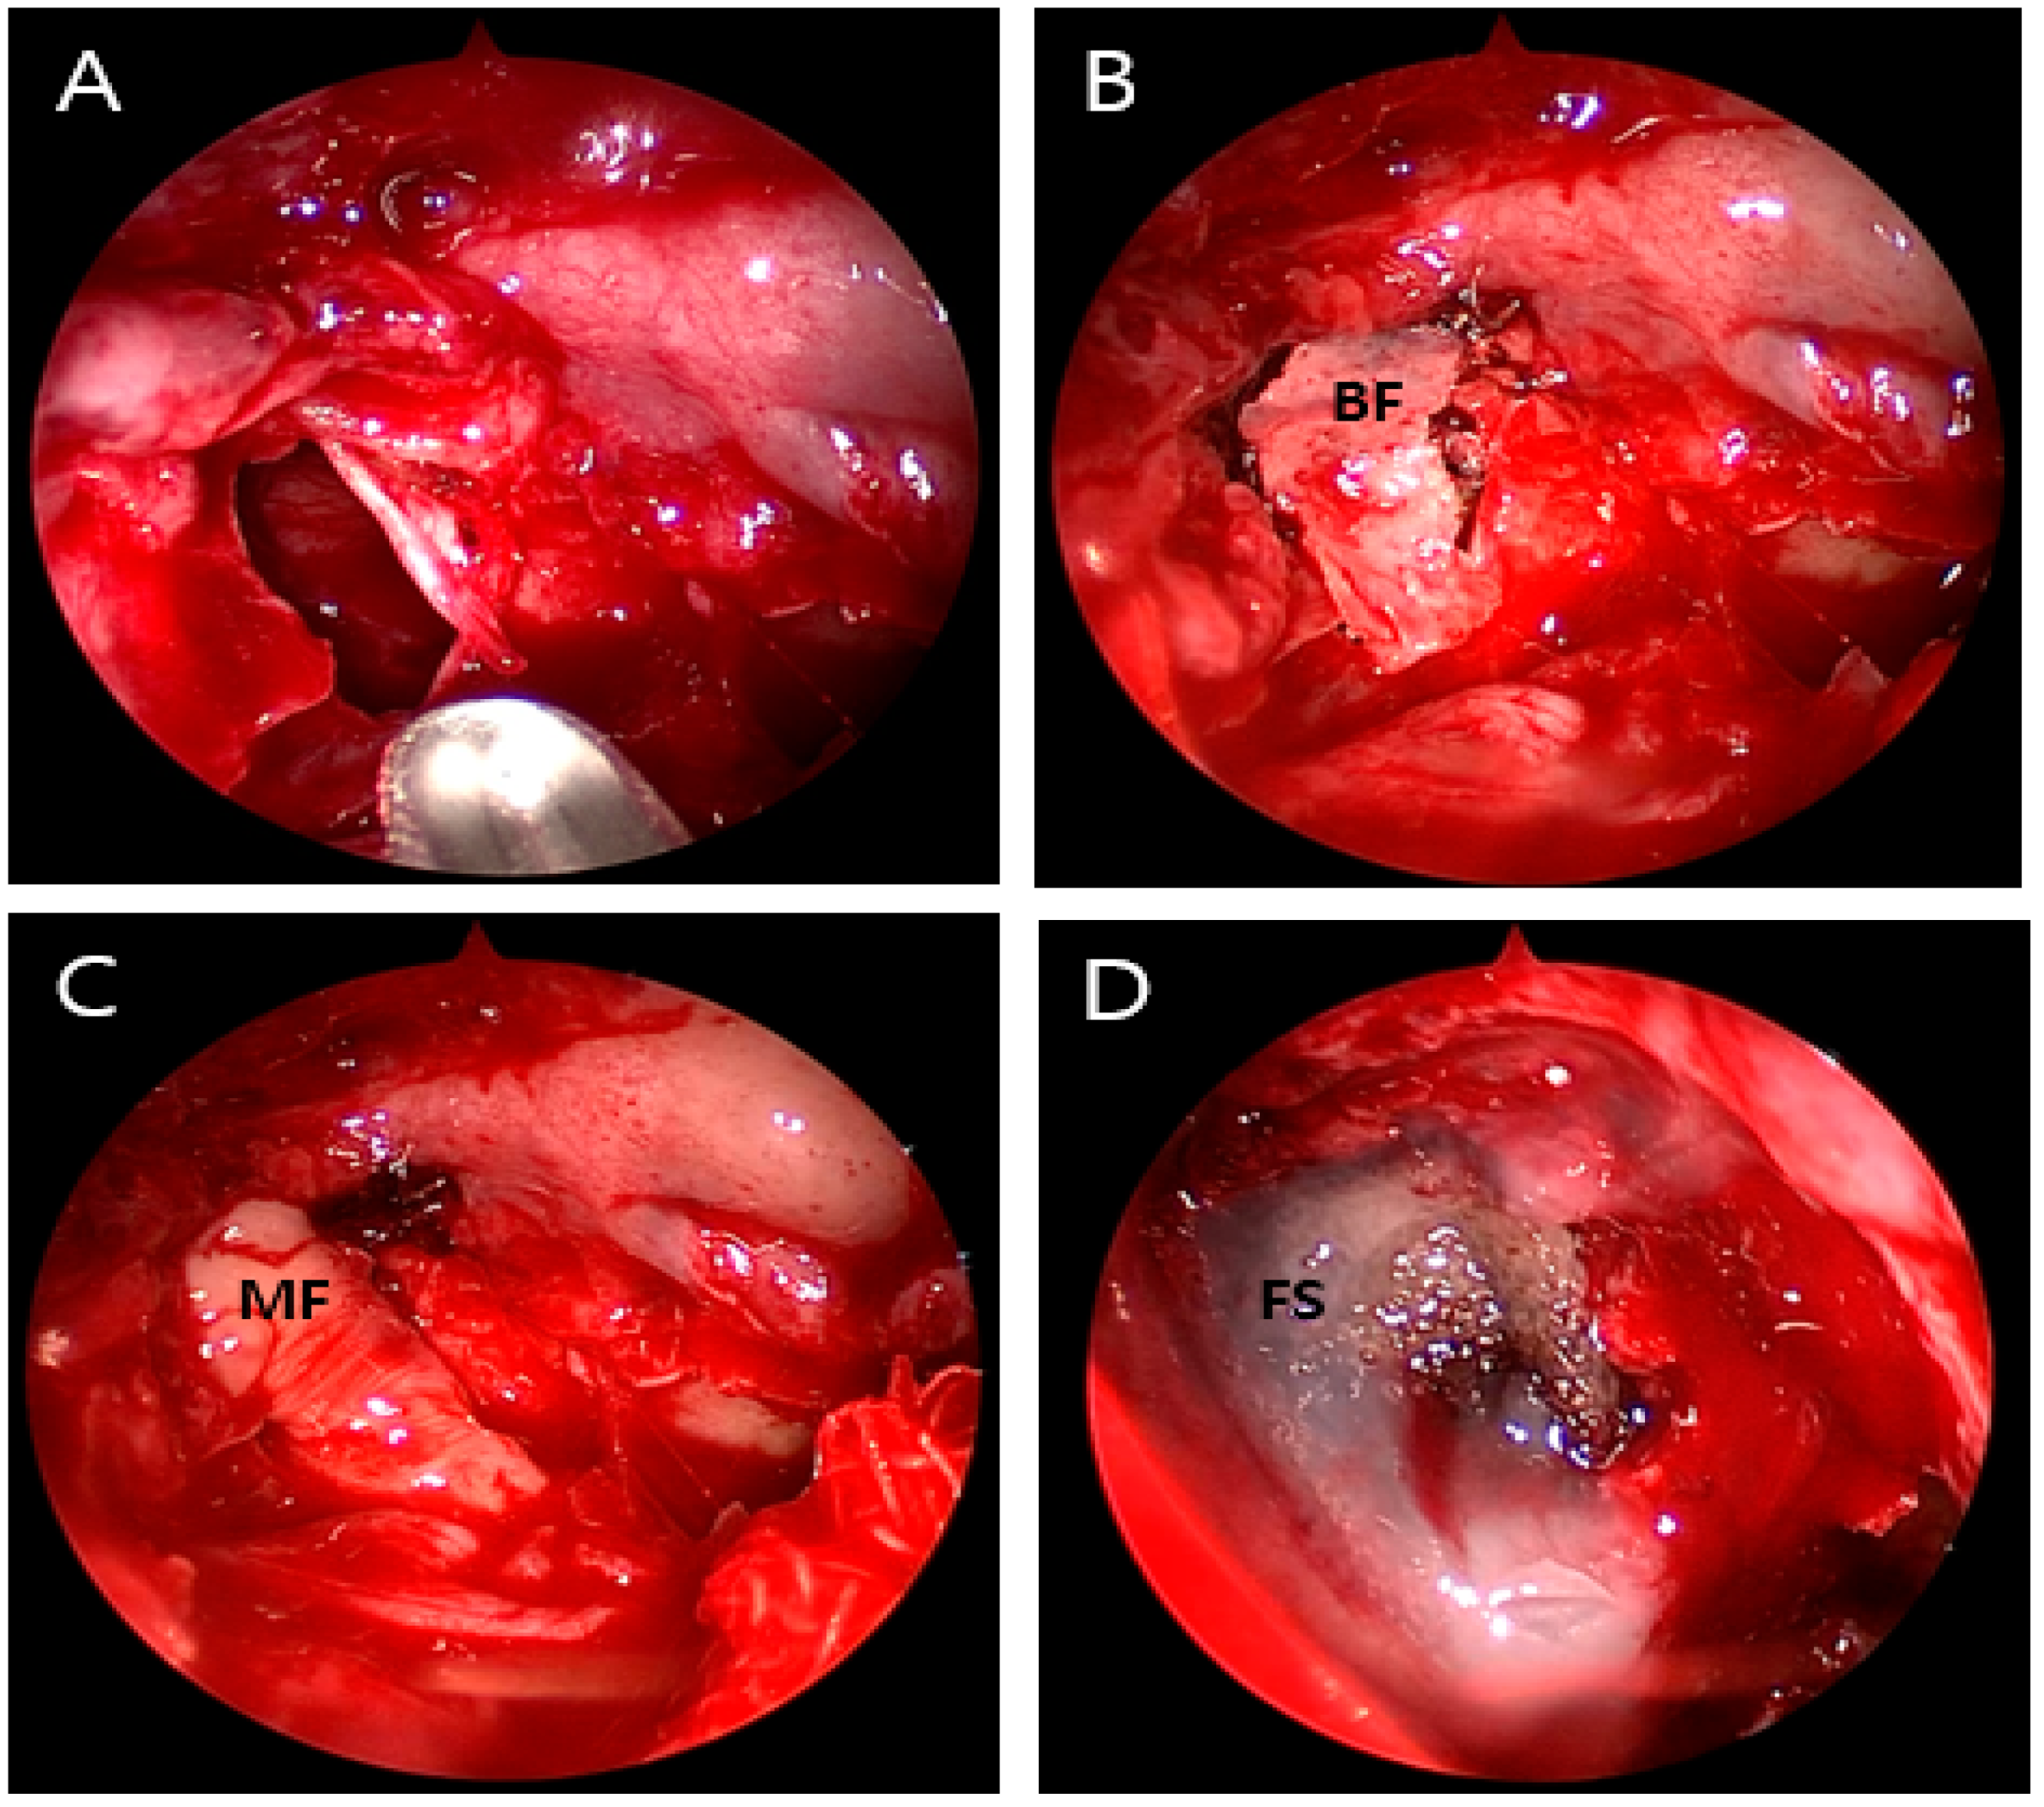

Intraoperative view images showing multi-layered closure of the dural and ethmoidal roof defect. (A) Bone defect (6 mm) on the horizontal (cribriform) plate of the ethmoid area. (B) Bone flap (indicated by ‘BF’). (C) Mucosal flap (MF). (D) Fibrin sealant (Evicel®) (FS).